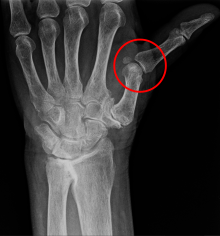

What is the MOI of wrist dislocation?

- Perilunate (lunate & capitate)

- Lunate (Lunate & radius)

A

1. Great force applied to extended wrist

- FOOSH

- MVA